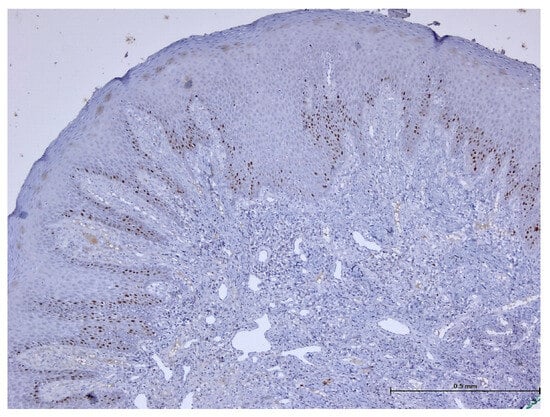

3. Results